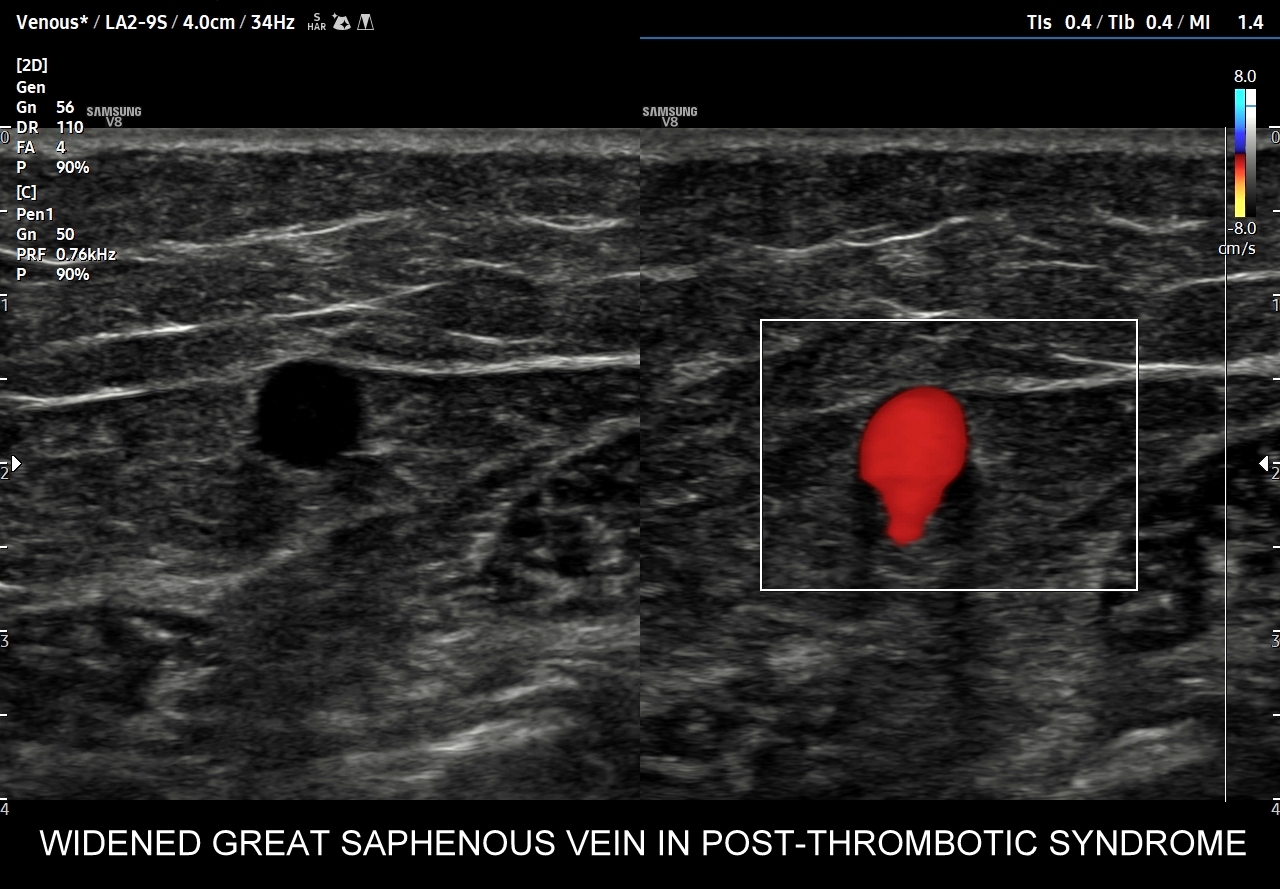

42. Patologie żył kończyn dolnych, w tym niewydolność żył powierzchownych i głębokich, żylaki, zakrzepica żył powierzchownych, zakrzepica żył głębokich, zespół pozakrzepowy.

Dzień żylny w ramach Kursu dedykowany jest dopplerowskiemu badaniu żył, w szczególności w obrębie kończyn dolnych. Otóż to właśnie w tym obszarze ujawniają się najczęściej choroby układu żylnego takie jak zakrzepica żył głębokich, zakrzepica żył powierzchownych, niewydolność żył powierzchownych i żylaki podudzi, niewydolność żył głębokich i zespół pozakrzepowy, które to badający lekarz powinien umieć rozpoznać. W trakcie interdyscyplinarnego Kurs USG Doppler Cedum ® omawiane są również hemodynamika krążenia żylnego w fizjologii i w stanach patologicznych; cele diagnostyczne, w tym planowanie zabiegów angiochirurgicznych i endowaskularnych w obrębie żył; a także nauczane są techniki funkcjonalnego badania żył kończyn dolnych i żył miednicy. Kurs obejmuje także tematykę dotycząca żyły głównej dolnej i jej brzusznych dopływów, żył szyjnych oraz żył kończyn górnych.